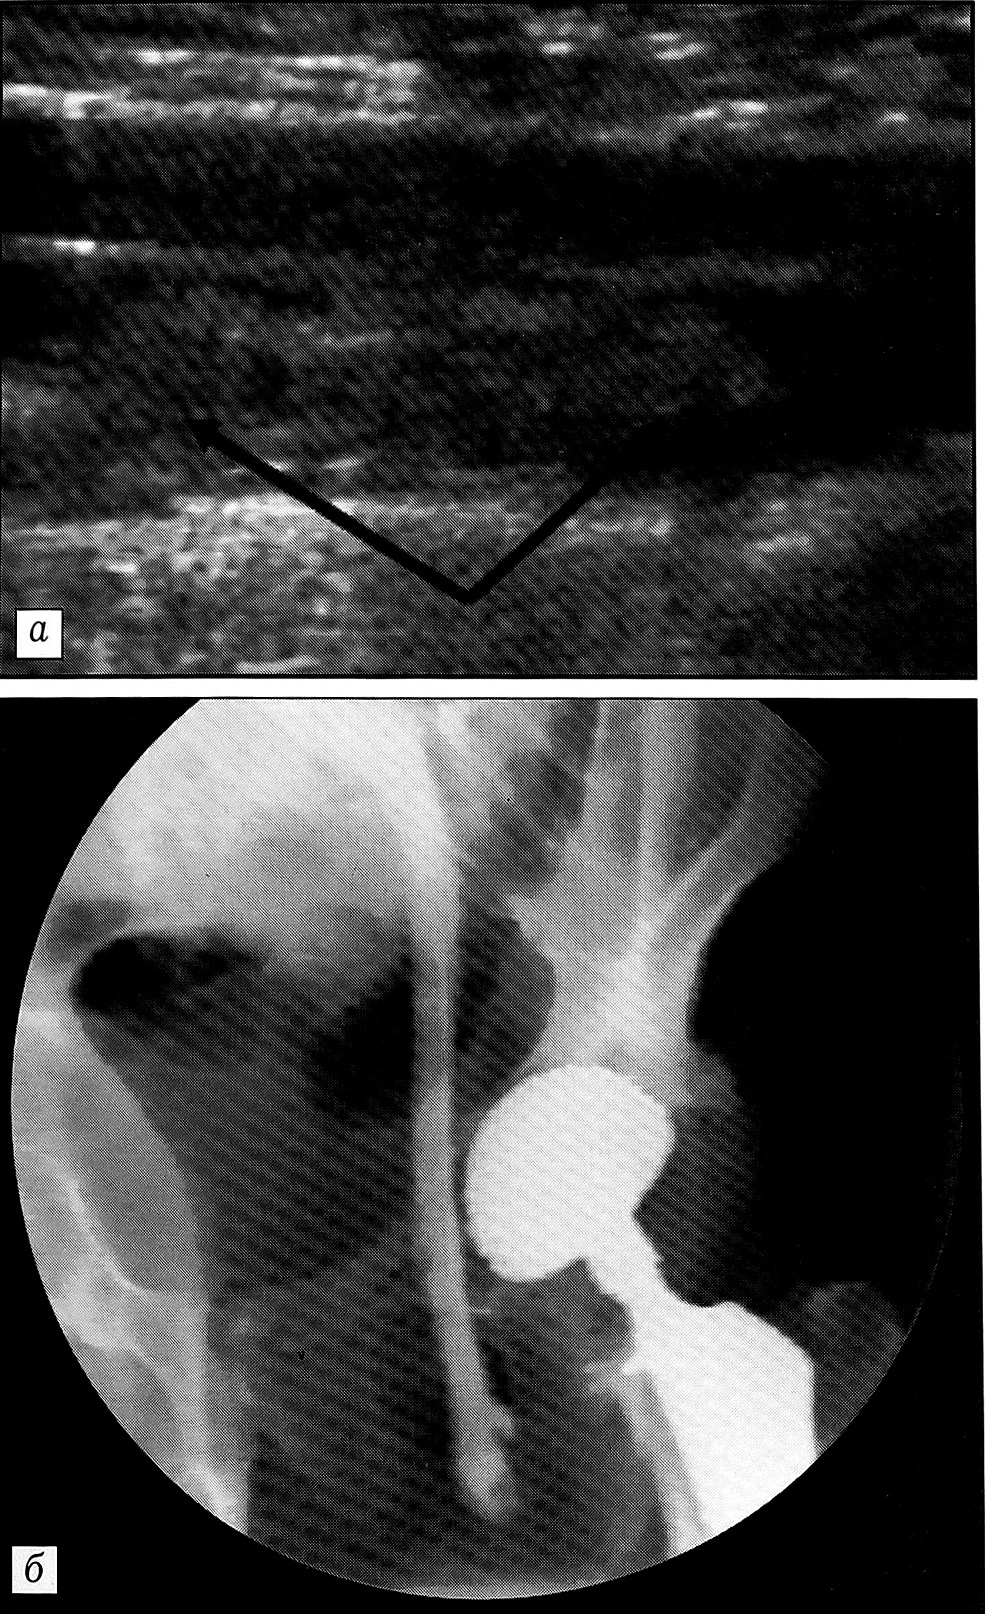

Тромбоэмболия легочной артерии развилась у одного из 14 пациентов с выявленным ТГВ (1,4% от общего числа обследованных). Это была больная 77 лет с переломом шейки бедра. Симптомы легочной эмболии появились на 4-е сутки после эндопротезирования тазобедренного сустава. В тот же день при ультразвуковом ангиосканировании выявлен флотирующий ТГВ с проксимальной границей в общей бедренной вене на контралатеральной конечности (рис. 3). Во время ретроградной илиокаваграфии установлен кава-фильтр.

Рис. 3. Ультрасонограмма (а) и флебограмма (б) конечности, контралатеральной по отношению к оперированной: флотирующий тромб в общей бедренной вене (стрелки).